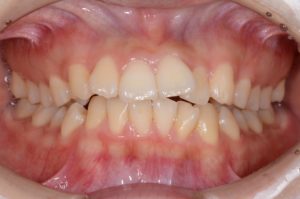

【スプリント治療後】

歯並びは変わっていませんが、顎の位置が正常に安定したことで

噛み合わせの位置が変化していることが分かります。

正しい位置で咬めるようになったためインビザラインに移行します。

【動的治療終了時】

スプリントの期間も合わせると約3年で歯並び、噛み合わせともにしっかり整いました。

この状態がキープできるようリテーナー(保定装置)に切り替え、保定期間に入ります。